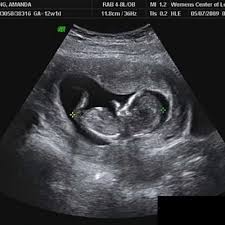

Im Ultraschall lassen sich nun die äußeren Geschlechtsorgane des Fötus. In Schwangerschaftswoche 14 ist Ihr Baby vom Schädel bis zum Steiß ungefähr 87 Zentimeter groß und wiegt 43 Gramm. Das tut sich in der 14.

Im Ultraschall lassen sich nun die äußeren Geschlechtsorgane des Fötus. Das Baby ist mittlerweile etwa 75 cm groß und 45 Gramm schwer. Die Entwicklung des Babys ist nach fünf Wochen der Schwangerschaft bereits vorangeschritten wobei im Ultraschall noch keine spannenden Entwicklungen zu sehen sind. Das Baby das jetzt ungefähr sieben Zentimeter lang ist kann in der 14. Schwangerschaftswoche Die Größe des Fötus ist ab der 14. Erfahren Sie mehr über die Entwicklung Ihres Kindes in der 14. Somit liegt der Kopf nicht mehr auf der Brust auf und nimmt eine zunehmend gerade Haltung ein.